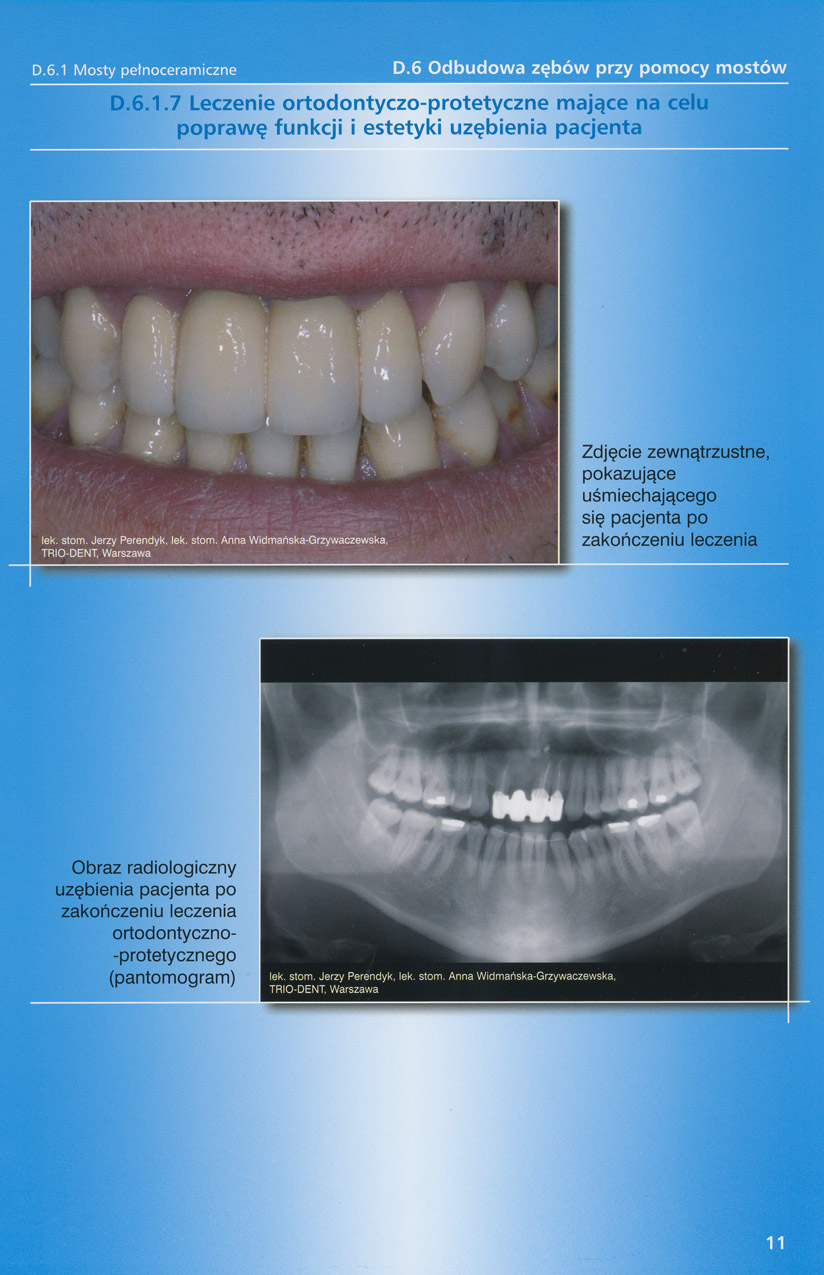

zobacz więcejGaleria przypadków klinicznych, obrazująca proces terapeutyczny od stanu wyjściowego aż do oddania ostatecznej pracy uzupełnienia brakującego uzębienia.